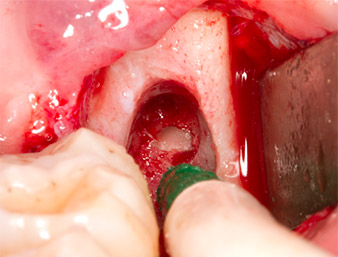

Pour exposer le reste radiculaire en minimisant le traumatisme causé aux tissus, un autre insert est utilisé (Piezomed S2) qui est principalement indiqué pour la préparation de la fenêtre latérale dans les élévations de plancher sinusien. La boule diamantée est également utilisée pour adoucir les bords osseux tranchants (Fig. 6 et 7). Tous les inserts Piezomed sont utilisés avec le paramétrage par défaut automatique, et sans la fonction Booster.

À l'aide d’un insert pour le débridement parodontal (Piezomed P1), l’espace ligamentaire parodontal de la racine résiduelle est ensuite élargi de manière minimale (Fig. 8).

Le même insert activé est inséré dans le canal radiculaire et détache le fragment sous l’effet de ses vibrations à micro-oscillations (Fig. 9, 10).

Il est ensuite possible, grâce à l’insert P1, d’extraire en un seul geste le reste radiculaire d’environ six millimètres de long (Fig. 11).

Le tissu périapical inflammé est également méticuleusement éliminé à l’aide d’une curette manuelle. La Fig. 12 représente l’alvéole vide et le nerf alvéolaire inférieur exposé.